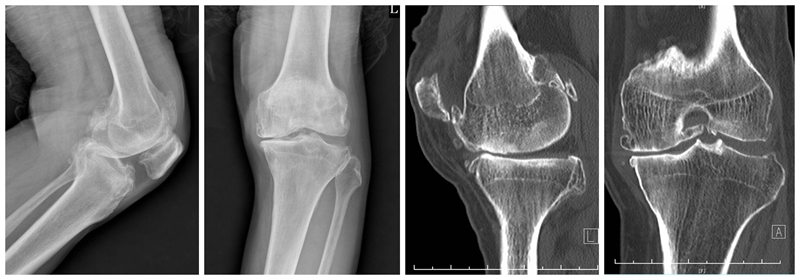

经典内侧单髁置换术(骨水泥型)

术前

术后检查

牛津单髁置换手术最经典的适应证是前内侧膝骨关节炎(AMOA),并且其他结构在功能上应保持完整,尤其强调韧带功能正常。在准备胫骨平台时,应保持7°后倾,截骨位置选在硬化骨下方,磨损最低点下方2mm处,近端紧贴,远端距皮缘18-20mm。试模间隙理想厚度6-7mm(包括胫骨假体3mm+垫片厚度3-4mm)。

在准备股骨侧时,理想状态为试模厚度刚好替换截骨厚度(约3mm),有5个关键点:(1)要保持韧带张力正常,避免过度松弛或过紧。(2)股骨假体位置保持良好,特别注意后髁截骨保持水平,去除骨赘,避免误判屈曲间隙。(3)股骨远端碾磨应保证内侧副韧带在屈膝110°和20°达到张力平衡。(4)要特别注意防撞击,保护内侧副韧带。(5)应采用2步法清除骨水泥。